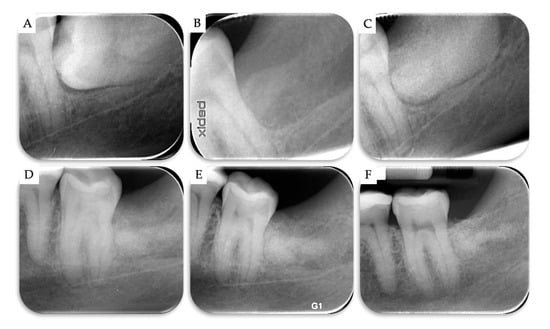

| Case | Gender | Age | Smoker | M3 | Impaction | Follow-Up (years) | PD T0 (mm) | PD T1 (mm) | BD T0 (mm) | BD T1 (mm) | BG (mm) |

|---|---|---|---|---|---|---|---|---|---|---|---|

| 1 | F | 51 | No | 48 | Mesio-angular | 2 | 12 | 3 | 11.1 | 5.2 | 5.86 |

| 2 | F | 36 | No | 38 | Horizontal | 2 | - | 1 | 7.4 | 1.3 | 6.1 |

| 3 | M | 42 | No | 38 | Horizontal | 1 | - | 2 | 10.2 | 4.4 | 5.79 |

| 4 | M | 34 | No | 48 | Horizontal | 1 | - | 2 | 8.6 | 2.1 | 6.51 |

| Mean | 40.75 | 1.5 | 2.00 | 9.33 | 3.25 | 6.07 | |||||

| SD | 6.61 | 0.5 | 0.71 | 1.43 | 1.6 | 0.28 |